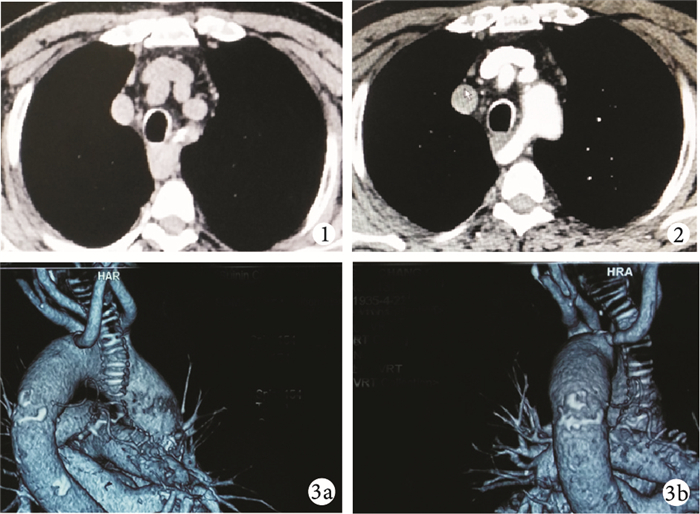

患者??男,77歲。因“進食梗阻1年”,于2015年4月21日入住我院消化內科。患者入院前1年開始出現進食梗阻,并逐漸加重,遂到我院消化內科就診。既往無明確吞咽功能障礙病史。體格檢查:胸部無特殊陽性體征。入院后經胸部CT平掃發現食管胸上段占位性病灶;胃鏡下顯示食管外壓性狹窄,食管黏膜光滑,考慮食管良性腫瘤。請胸外科會診擬行手術切除。經胸外科再次閱片發現病灶在后縱隔向上延續,且在正常解剖位未發現右側鎖骨下動脈,遂考慮異常血管可能(圖 1)。再次行胸部增強CT檢查證實患者為右側鎖骨下動脈直接從主動脈弓分支并經過氣管食管后方到達鎖骨下(圖 2)。由此確定患者進食梗阻原因并非由食管本身病灶,而是由迷走的鎖骨下動脈壓迫所致(圖 3)。鑒于患者梗阻癥狀較輕,不需特殊處理,與患者溝通后建議患者出院隨訪。出院6個月后隨訪,患者進食梗阻的癥狀無明顯變化,囑繼續門診隨訪。

胸部CT平掃圖????見食管胸上段占位病灶??圖 2 ?胸部CT增強圖????見食管胸上段占位實為從氣管及食管后方經過的右側鎖骨下動脈,食管位于二者之間??圖 3 ?CT血管三維重建圖????3a、3b. ?可見右側鎖骨下動脈直接起始于主動脈弓并經過氣管的后方